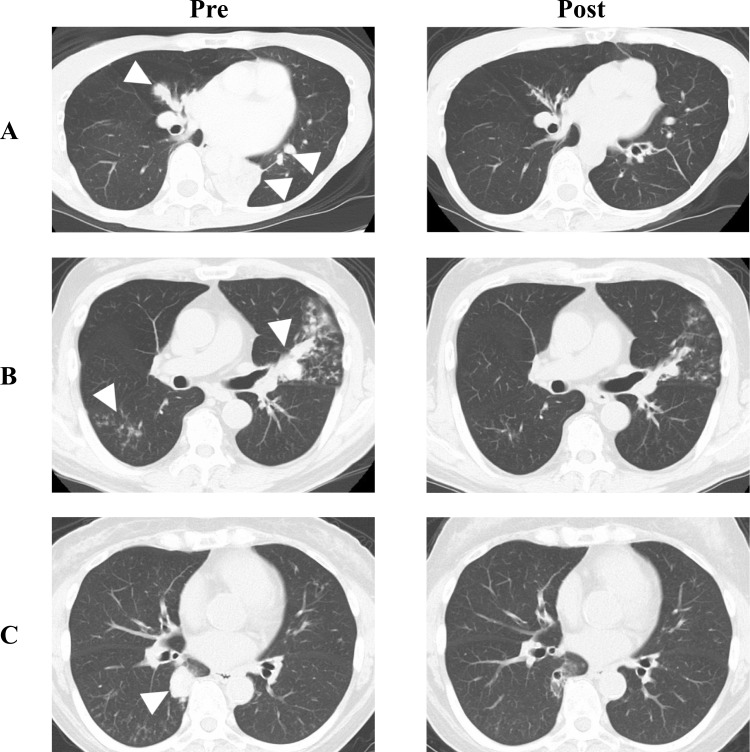

过敏性支气管肺曲霉菌病的特点是对曲霉菌过敏,常引起难治性哮喘。对过敏性支气管肺曲霉病患者使用的生物制剂进行了研究;然而,治疗并不总是成功的。这可能是由于目前选择性靶向单一细胞因子的生物制剂的局限性。Tezepelumab是一种阻断胸腺基质淋巴生成素活性的人单克隆抗体,通过调节气道炎症的上游级联,广泛抑制2型炎症。因此,有望对过敏性支气管肺曲菌病患者有良好的疗效。我们报告三例变应性支气管肺曲霉病,尽管最大限度地使用传统的抗哮喘药物,如吸入剂,抗白三烯受体拮抗剂和抗真菌药物,但症状不受控制。这些患者此前均未接受过生物制剂治疗。tezepelumab的加入在所有3例患者中产生了显着的临床反应,包括更少的恶化和口服全身皮质类固醇和/或按需减少短效β -2激动剂的剂量。患者肺部症状得到较好的控制,外周血嗜酸性粒细胞计数和免疫球蛋白E水平下降,生活质量评分和呼吸功能参数改善。胸部计算机断层扫描观察到的粘膜塞伴肺不张和浸润影也有所改善。Tezepelumab可能是严重哮喘患者过敏性支气管肺曲霉病的一个有希望的治疗选择,提供有效的症状控制和减少全身皮质类固醇的使用。

Allergic bronchopulmonary aspergillosis is characterized by hypersensitivity to Aspergillus spp. and often causes intractable asthma. Studies have been conducted on biologics administered to patients with allergic bronchopulmonary aspergillosis; however, treatment may not always be successful. This may be due to the limitations of the current biologics that selectively target a single cytokine. Tezepelumab, a human monoclonal antibody that blocks the activity of thymic stromal lymphopoietin, broadly suppresses type 2 inflammation by regulating the upstream cascade of airway inflammation. Therefore, it is expected to have favorable effects in patients with allergic bronchopulmonary aspergillosis. We report three cases of allergic bronchopulmonary aspergillosis with uncontrolled symptoms despite the maximal use of conventional anti-asthmatic drugs such as inhalative agents, anti-leukotriene receptor antagonists, and antifungal drugs. None of the patients had previously received biologics. The addition of tezepelumab produced a marked clinical response in all three patients, which included fewer exacerbations and a reduced dosage of oral systemic corticosteroids and/or reduced as-needed short-acting beta-2 agonists. The patients' pulmonary symptoms were better controlled, peripheral blood eosinophil counts and immunoglobulin E levels decreased, and quality of life scores and respiratory function parameters improved. Mucous plugs accompanied by atelectasis and infiltrative shadows observed on chest computed tomography also improved. Tezepelumab may be a promising treatment option for allergic bronchopulmonary aspergillosis in patients with severe asthma, offering effective symptom control and enabling reduction in systemic corticosteroid use.